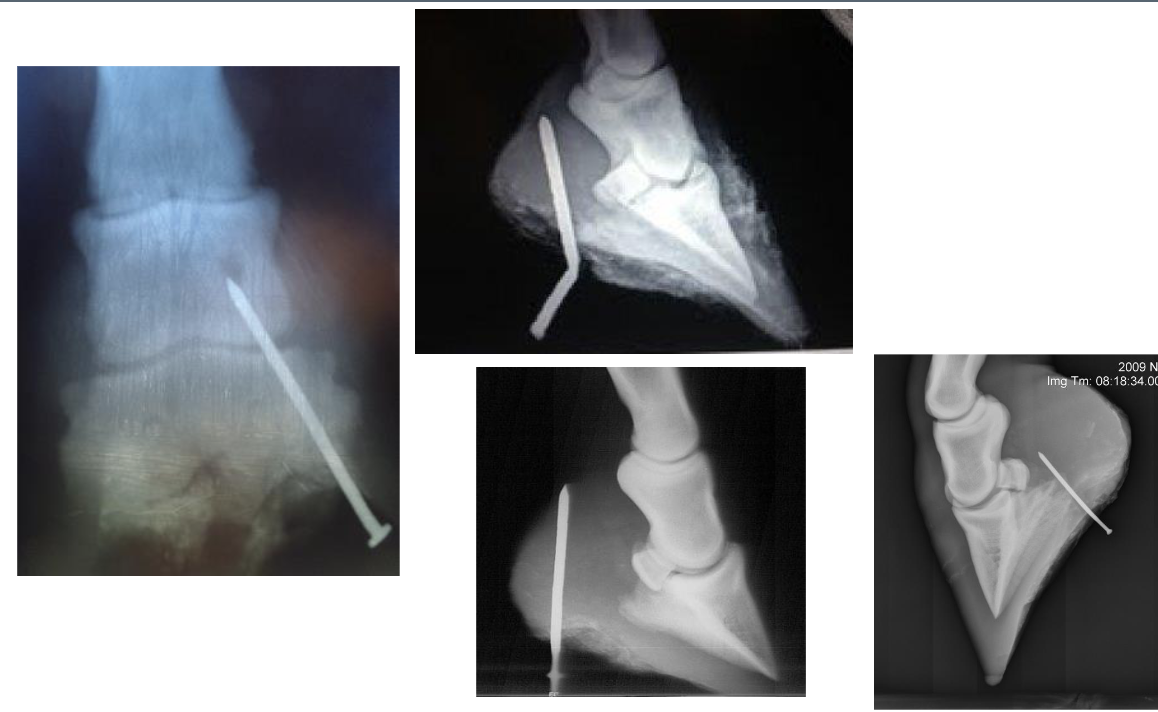

what tendons are torn for these lacerations (L to R)

SDFT only

SDFT & DDFT

SDFT, DDFT, & SL (completely plantigrade)

gastrocnemius lacerations, left to right

normal

gastrocnemeus only (plantigrade stance)

gastroc & SDFT → cannot stand